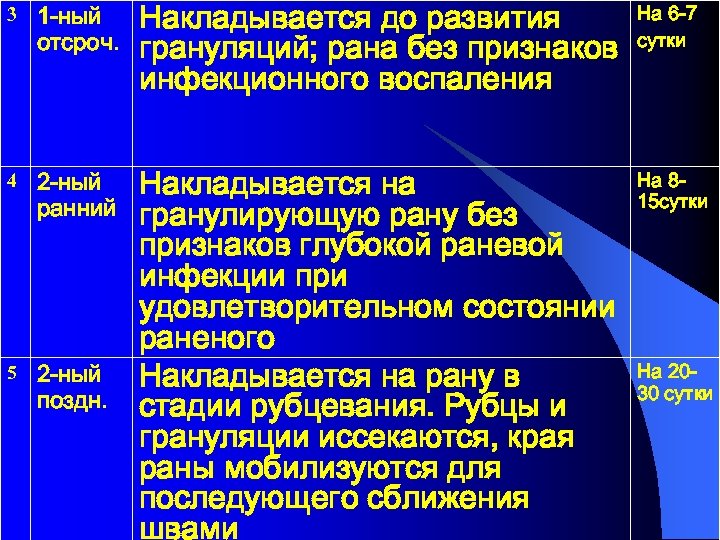

Наложение ранних вторичных швов на гранулирующую рану

Наложение ранних вторичных швов на гранулирующую рану